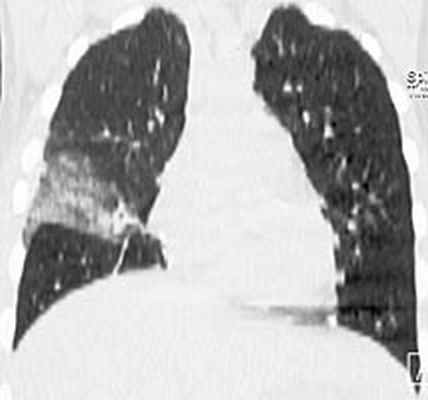

У пациента подтвержден диагноз острого инфекционного эндокардита, недостаточность митрального клапана 3 ст, церебральная эмболия с развитием менингоэнцефалита. Была продолжена терапия ванкомицином и таваником, на фоне которой сохранялась фебрильная лихорадка до 38,5С, в связи с чем проведена смена антибактериальной терапии на линезолид 1,2 г/сут. Однако на фоне терапии сохранялась лихорадка 37,8С. Наличие неконтролируемой инфекции, перенесенная эмболия, наличие крупной вегетации на митральном (наиболее эмбологенном) клапане, явились показанием к протезированию клапана. Осмотрен кардиохирургом. На 7 сутки пребывания в стационаре больному выполнена операция (академиком РАН Шевченко Ю.Л.) санации камер сердца, протезирование митрального клапана протезом Мединдж – 25 в условиях искусственного кровообращения и фармакохолодовой кардиоплегии. Интраоперационно у основания передней створки митрального клапана обнаружен абсцесс диаметром до 1 см. В послеоперационном периоде продолжена терапия ванкомицином 2 г/сут, ципрофлоксацином 0,8 г/сут. На фоне терапии сохранялась лихорадка до 37,9С. В связи с этим пациенту выполнена компьютерная томография органов грудной клетки:

В средней доле правого легкого массивный участок снижения воздушности легочной ткани с очагами инфильтрации, занимающий практически весь объем доли. Диагностирована госпитальная пневмония в средней доле правого легкого. Учитывая сохраняющуюся лихорадку, проведена смена комбинированной антибактериальной терапии на тиенам 2 г/сут в сочетании с линдацином 2г/сут. Лишь после назначения авелокса 0,4 г/сут с римфапицином 0,6 г/сут достигнута стойкая нормализация температуры тела, исчезновение инфильтративных изменений в легких. Нормализовались лабораторные показатели: гем. – 126 г/л, лейк. 8,1х109/л, п - 1%, с – 38%, СОЭ 12 мм/час. Контрольная чрезпищеводная ЭхоКГ без патологии. В течение последующих 1,5 лет рецидива инфекции не было. Температура тела, ЭхоКГ, лабораторные показатели в норме. Клиническое наблюдение представлено острым по началу инфекционным эндокардитом, при котором летальность приближается к 100%. Антибактериальная терапия как и в нашем наблюдении, редко бывает эффективной. Обычно в ранние сроки, особенно при поражении митрального клапана, развиваются множественные эмболии. Хирургическое лечение должно выполнятся как можно раньше, промедление с операцией могло привести к развитию новых более грозных осложнений, которые могли стать непреодолимым препятствием к хирургическому лечению. Современная оперативная техника позволяет не дожидаться санации клапана антибиотиками, а провести хирургическую санацию очага внутрисердечной инфекции в ранние сроки заболевания при наличии показаний к операции.